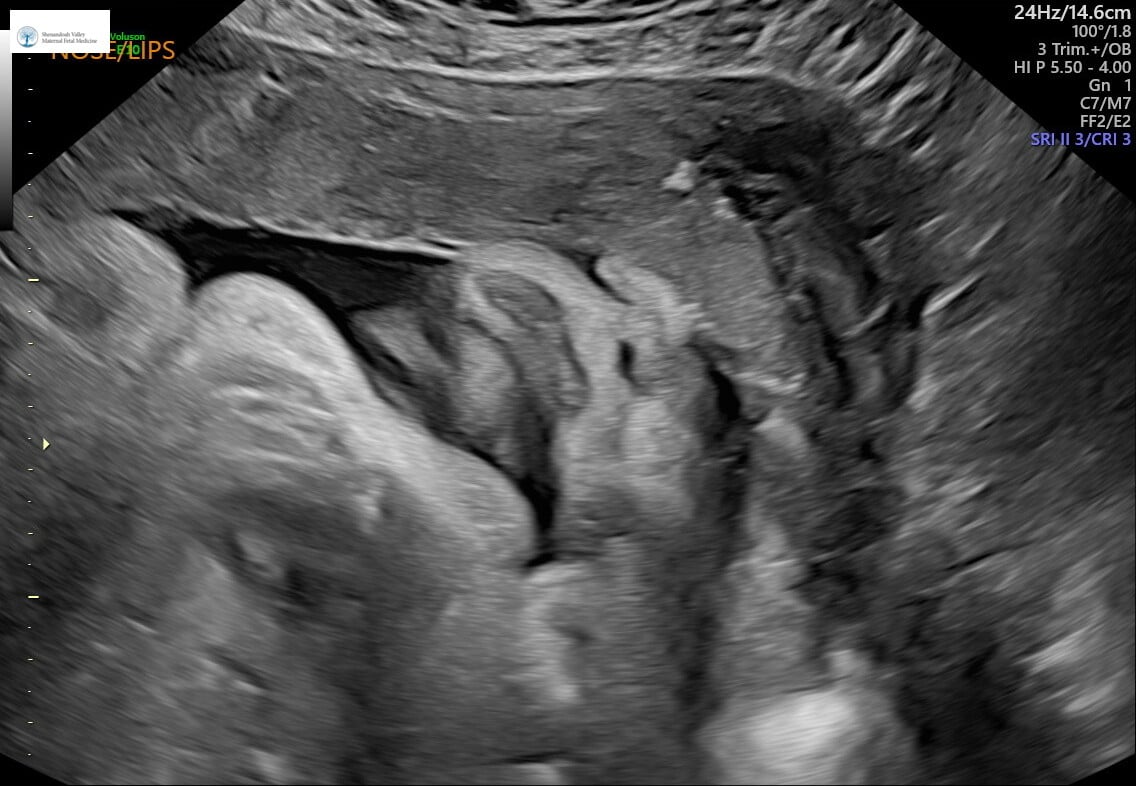

squishy face for attention: